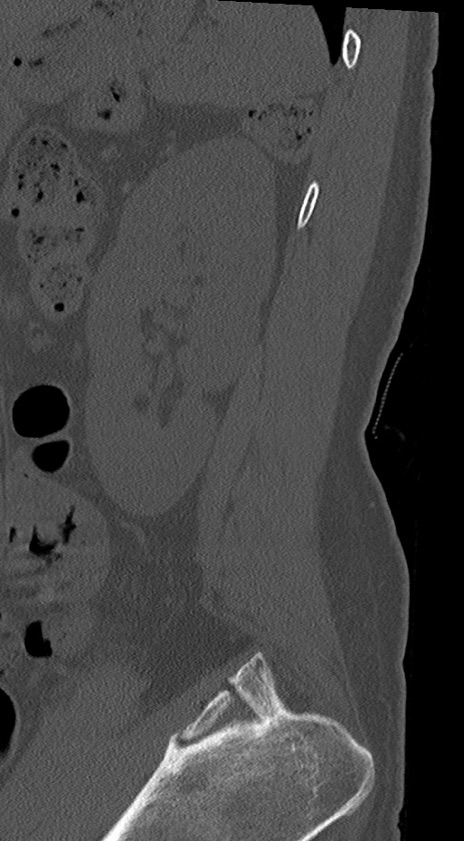

【整形】TIPS症例4 腰椎CT(矢状断像)

腰椎CT